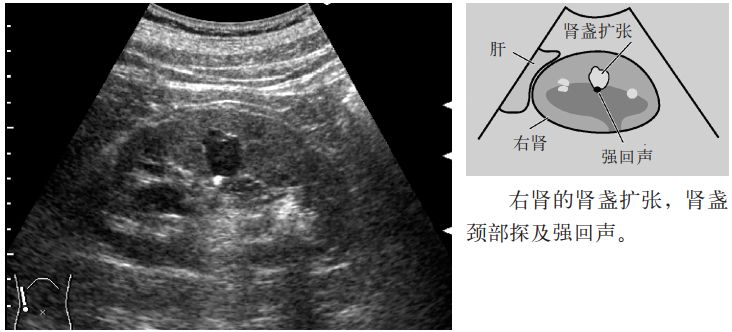

5.因肾盏漏斗部狭窄而致的肾盏扩张称为肾盏积水(hydrocalycosis)。肾盏扩张可以是单个或多个。其原因除了先天性漏斗部狭窄或巨大肾盏症外,也见于肾盏结石造成的狭窄。应与肾盏憩室或肾积水相鉴别,肾盏积水表现为与正常肾盏部分相同的囊肿样无回声区,其内大多数可探及钙乳或结石。

图6 肾盏积水